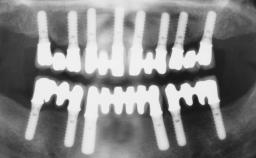

Two dental implants are placed in the same surgical session. The case concludes with the presentation of the final fixed dental prosthesis with a distal cantilever unit.

The 1-year follow-up radiographs demonstrate successful sinus floor elevation and stable bone crest levels around both implants, leading to a favorable long-term prognosis of the implant-supported prosthesis.